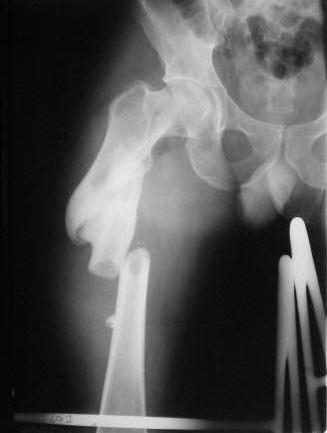

Пример с антеградным введением стержня (застарелый случай)

У тебя тоже можно воспользоваться этой методой, однако настоятельно рекомендую ЗИМО делать в аппарате (дистракционном устройстве) и лишь потом открыто вертлугу.

Глубокоуважаемые коллеги! Благодарю за полезные советы, которые нам очень помогли в выборе оперативной тактики пациента. 13.02.08 мы выполнили первый этап оперативного лечения этого больного. Вначале зафиксировали левое бедро АВФ Гофмана

(главный травматолог области достал из каких-то «анналов», первый раз в жизни увидел этот аппарат в живую). После наложения «ДРУ Челнокова» выполнили ЗИО правого бедра реконструктивным штифтом Chm. Далее уложили пациента на левый бок и выполнили остеосинтез вертлужной впадины. Ограничились задне-латеральным доступом без отсечения вертела, чтобы не утяжелять операцию. Результат прилагается.